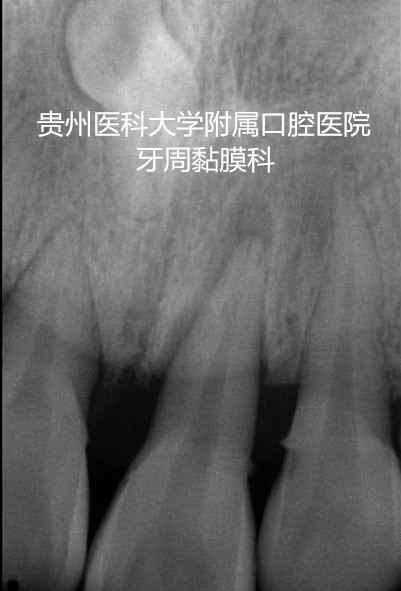

陈老师是一名重度牙周炎的患者,上下前牙多颗牙松动严重,经过牙周系统治疗后,牙周的炎症得到控制,但上下前牙的松动仍影响咬合,经过小艾电竞官方网站牙周黏膜科的高强度纤维带松牙固定后,将多个松动牙连成一个新的咀嚼单位,有利于牙周组织的愈合,陈老师非常满意。